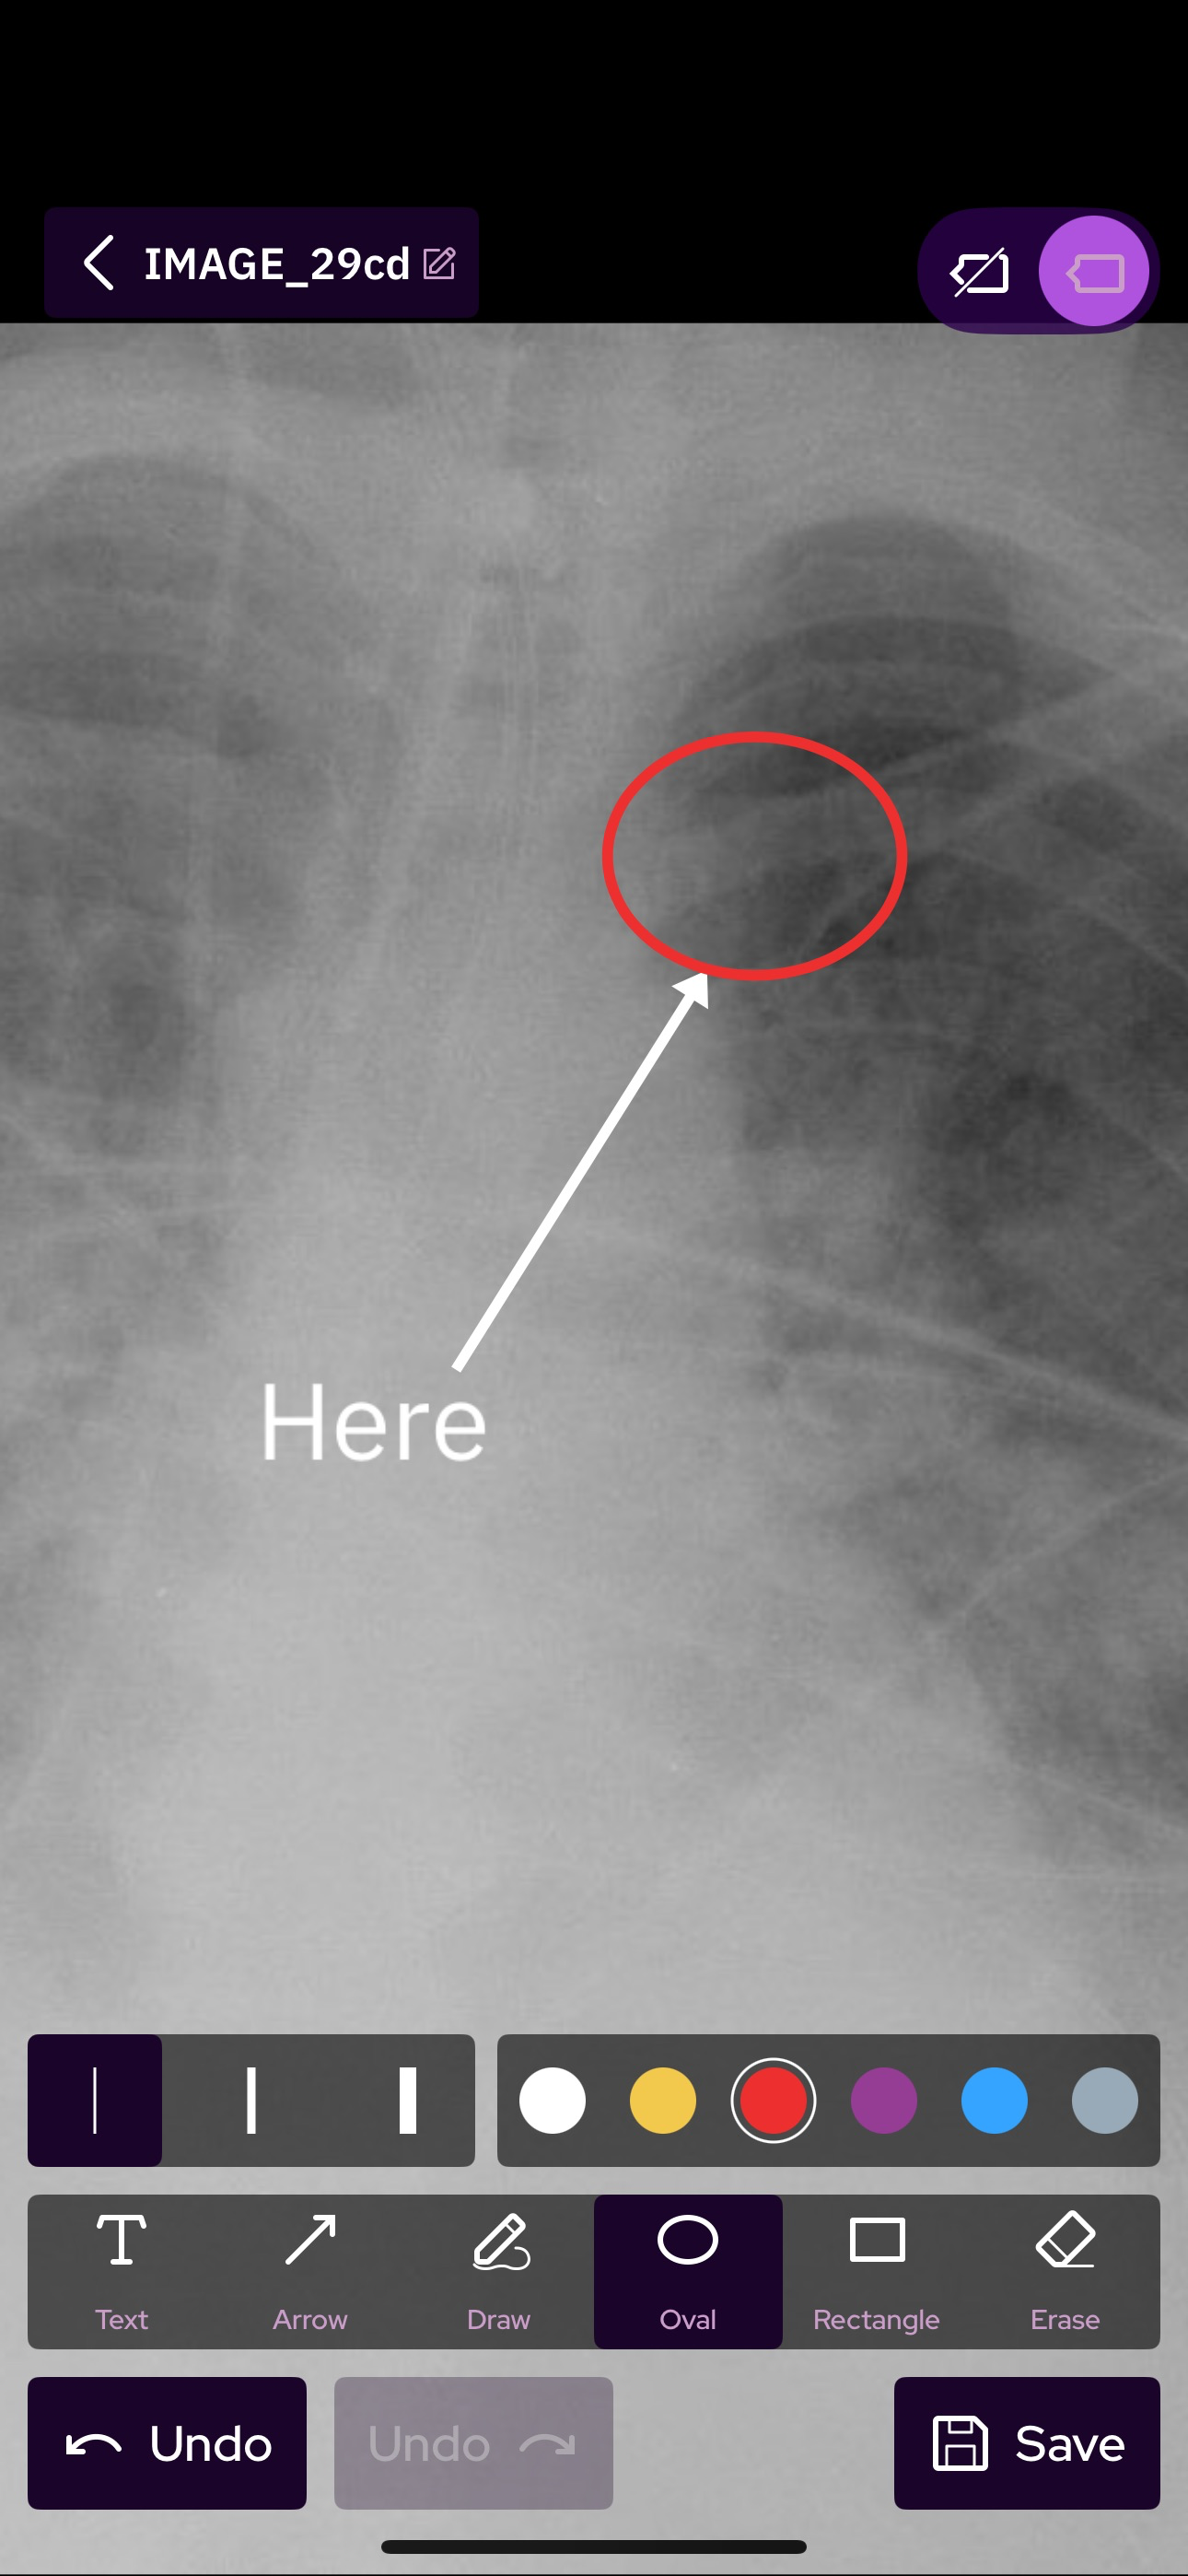

SeaGreen is a secure, open, free to use platform for healthcare professional to connect and collaborate. SeaGreen streamline consultation and collaboration such as AI powered capture mode that anonymize and a software virtual operating room.